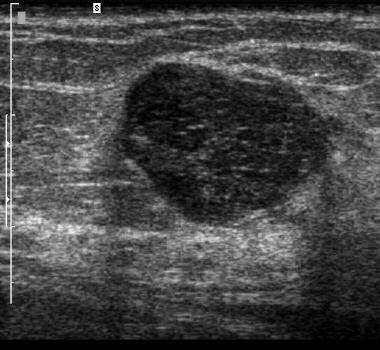

The target dataset was developed from 35 breast ultrasound scans that were segmented by an image-processing expert with extensive experience in breast lesion segmentation (the second author). The images, collected from the Web, are of different dimensions, ranging from to pixels (Figure 3, images resized for sake of illustration). These are the same images used to introduce EFIS originally [1].

Ultrasound images are generally difficult to segment, primarily due to the presence of speckle noise and low level of local contrast. It should be noted that the segmentation of ultrasound actually does require a complete processing chain, (including proper preprocessing and post-processing steps). However, the purpose of using these images was solely to demonstrate that the accuracy of the segmentation can be increased with the application of SC-EFIS.